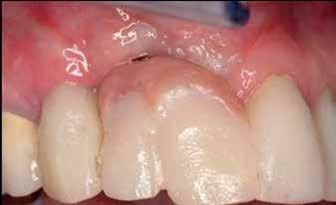

A 45-year-old female patient, with a history of smoking, presented to a private periodontal practice after experiencing an unsuccessful ridge-augmentation procedure at a university periodontal clinic. Originally, tooth #7 was surgically extracted and the socket was augmented. This procedure was not successful due to soft tissue complications and possibly smoking. She subsequently underwent a surgical procedure involving the use of a titanium mesh, combined with a bone allograft hydrated with rhPDGF-BB. Early exposure of the mesh and local site infection resulted in the removal of the mesh and debridement of non-incorporated bone graft materials. This resulted in a significant ridge-defect (Fig. 1).

One of the titanium fixation tacks was left in place at this time. The patient was provisionalized from tooth #6 through #11 with a fixed restoration. Her general dentist determined tooth #8 to be nonrestorable due to caries. She was referred to a private periodontal office for extraction of the carious central incisor and ridge-augmentation in the #7 and #8 locations. Previous endodontic therapy and guarded crown-to-root ratio of #6 was determined to be a questionable distal bridge abutment for a long-span fixed partial denture (FPD), and implant therapy was requested by the restorative dentist and patient. The first surgery was geared towards extraction of the carious root of tooth #8, the removal of the fixation tack left behind by the previous surgeon and bone augmenation. The plan was to combine an

Approximately four months after bone augmentation surgery, a subepithelial connective tissue graft was performed to increase the width and thickness of keratinized mucosa in the anticipated implant-placement sites (Fig. 6).

Figure 6: Approximately 4 months after hard tissue grafting, a soft tissue graft was secured from the palatal mucosa of the premolar region. This was done to increase the zone of keratinized mucosa and increase mucosal thickness.

After approximately 2 months healing, both healing abutments are partially-exposed. When the healing abutment on the #7 position implant was loosened, there was detectable movement of the implant fixture. The healing abutment was re-tightened. The #8 healing abutment was easily removed and a fixture level impression was taken. A screw-retained provisional restoration, supported by the single, central incisor implant was indirectly fabricated. An additional healing period of 8 weeks preceded utilization of this implant for fixation of the temporary restoration. During this time, a restorative post and core and new temporary crown was fabricated to improve retention of a single-unit provisional crown on tooth #6. The provisional FPD was sectioned between #6 and #7 and the patient presented for implant temporization. A minor mucoplasty around the #8 implant was done to facilitate access to the healing abutment and its removal. Prior to seating the cantilevered provisional restoration, the healing abutment on the #7 implant was painlessly removed and re-tightened without any tactile movement of the implant or discomfort. The provisional restoration, which incorporated pink and tooth-colored composite resin was adjusted and tightened to 15 ncm (Figs. 13-15).

Figure 13: Four months after implant placement, a screw- retained provisional restoration was placed, supported by the implant in the #8 position. This was done following post and core placement in tooth #6 and fabrication of a single, temporary crown on the canine.